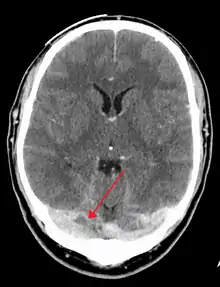

CT venogram showing a filling defect in the sagittal sinus (black arrow)

A dural venous sinus thrombosis of the transverse sinus. Greater on the right than left.

There are various neuroimaging investigations that may detect cerebral sinus thrombosis. Cerebral edema and venous infarction may be apparent on any modality, but for the detection of the thrombus itself, the most commonly used tests are computed tomography (CT) and magnetic resonance imaging (MRI), both using various types of radiocontrast to perform a venogram and visualise the veins around the brain.[3]

Computed tomography, with radiocontrast in the venous phase (CT venography or CTV), has a detection rate that in some regards exceeds that of MRI. The test involves injection into a vein (usually in the arm) of a radioopaque substance, and time is allowed for the bloodstream to carry it to the cerebral veins – at which point the scan is performed. It has a sensitivity of 75–100% (it detects 75–100% of all clots present), and a specificity of 81–100% (it would be incorrectly positive in 0–19%). In the first two weeks, the "empty delta sign" may be observed (in later stages, this sign may disappear).[11] The empty delta sign is characterized by enhancement of the dural wall without intra-sinus enhancement.[6]